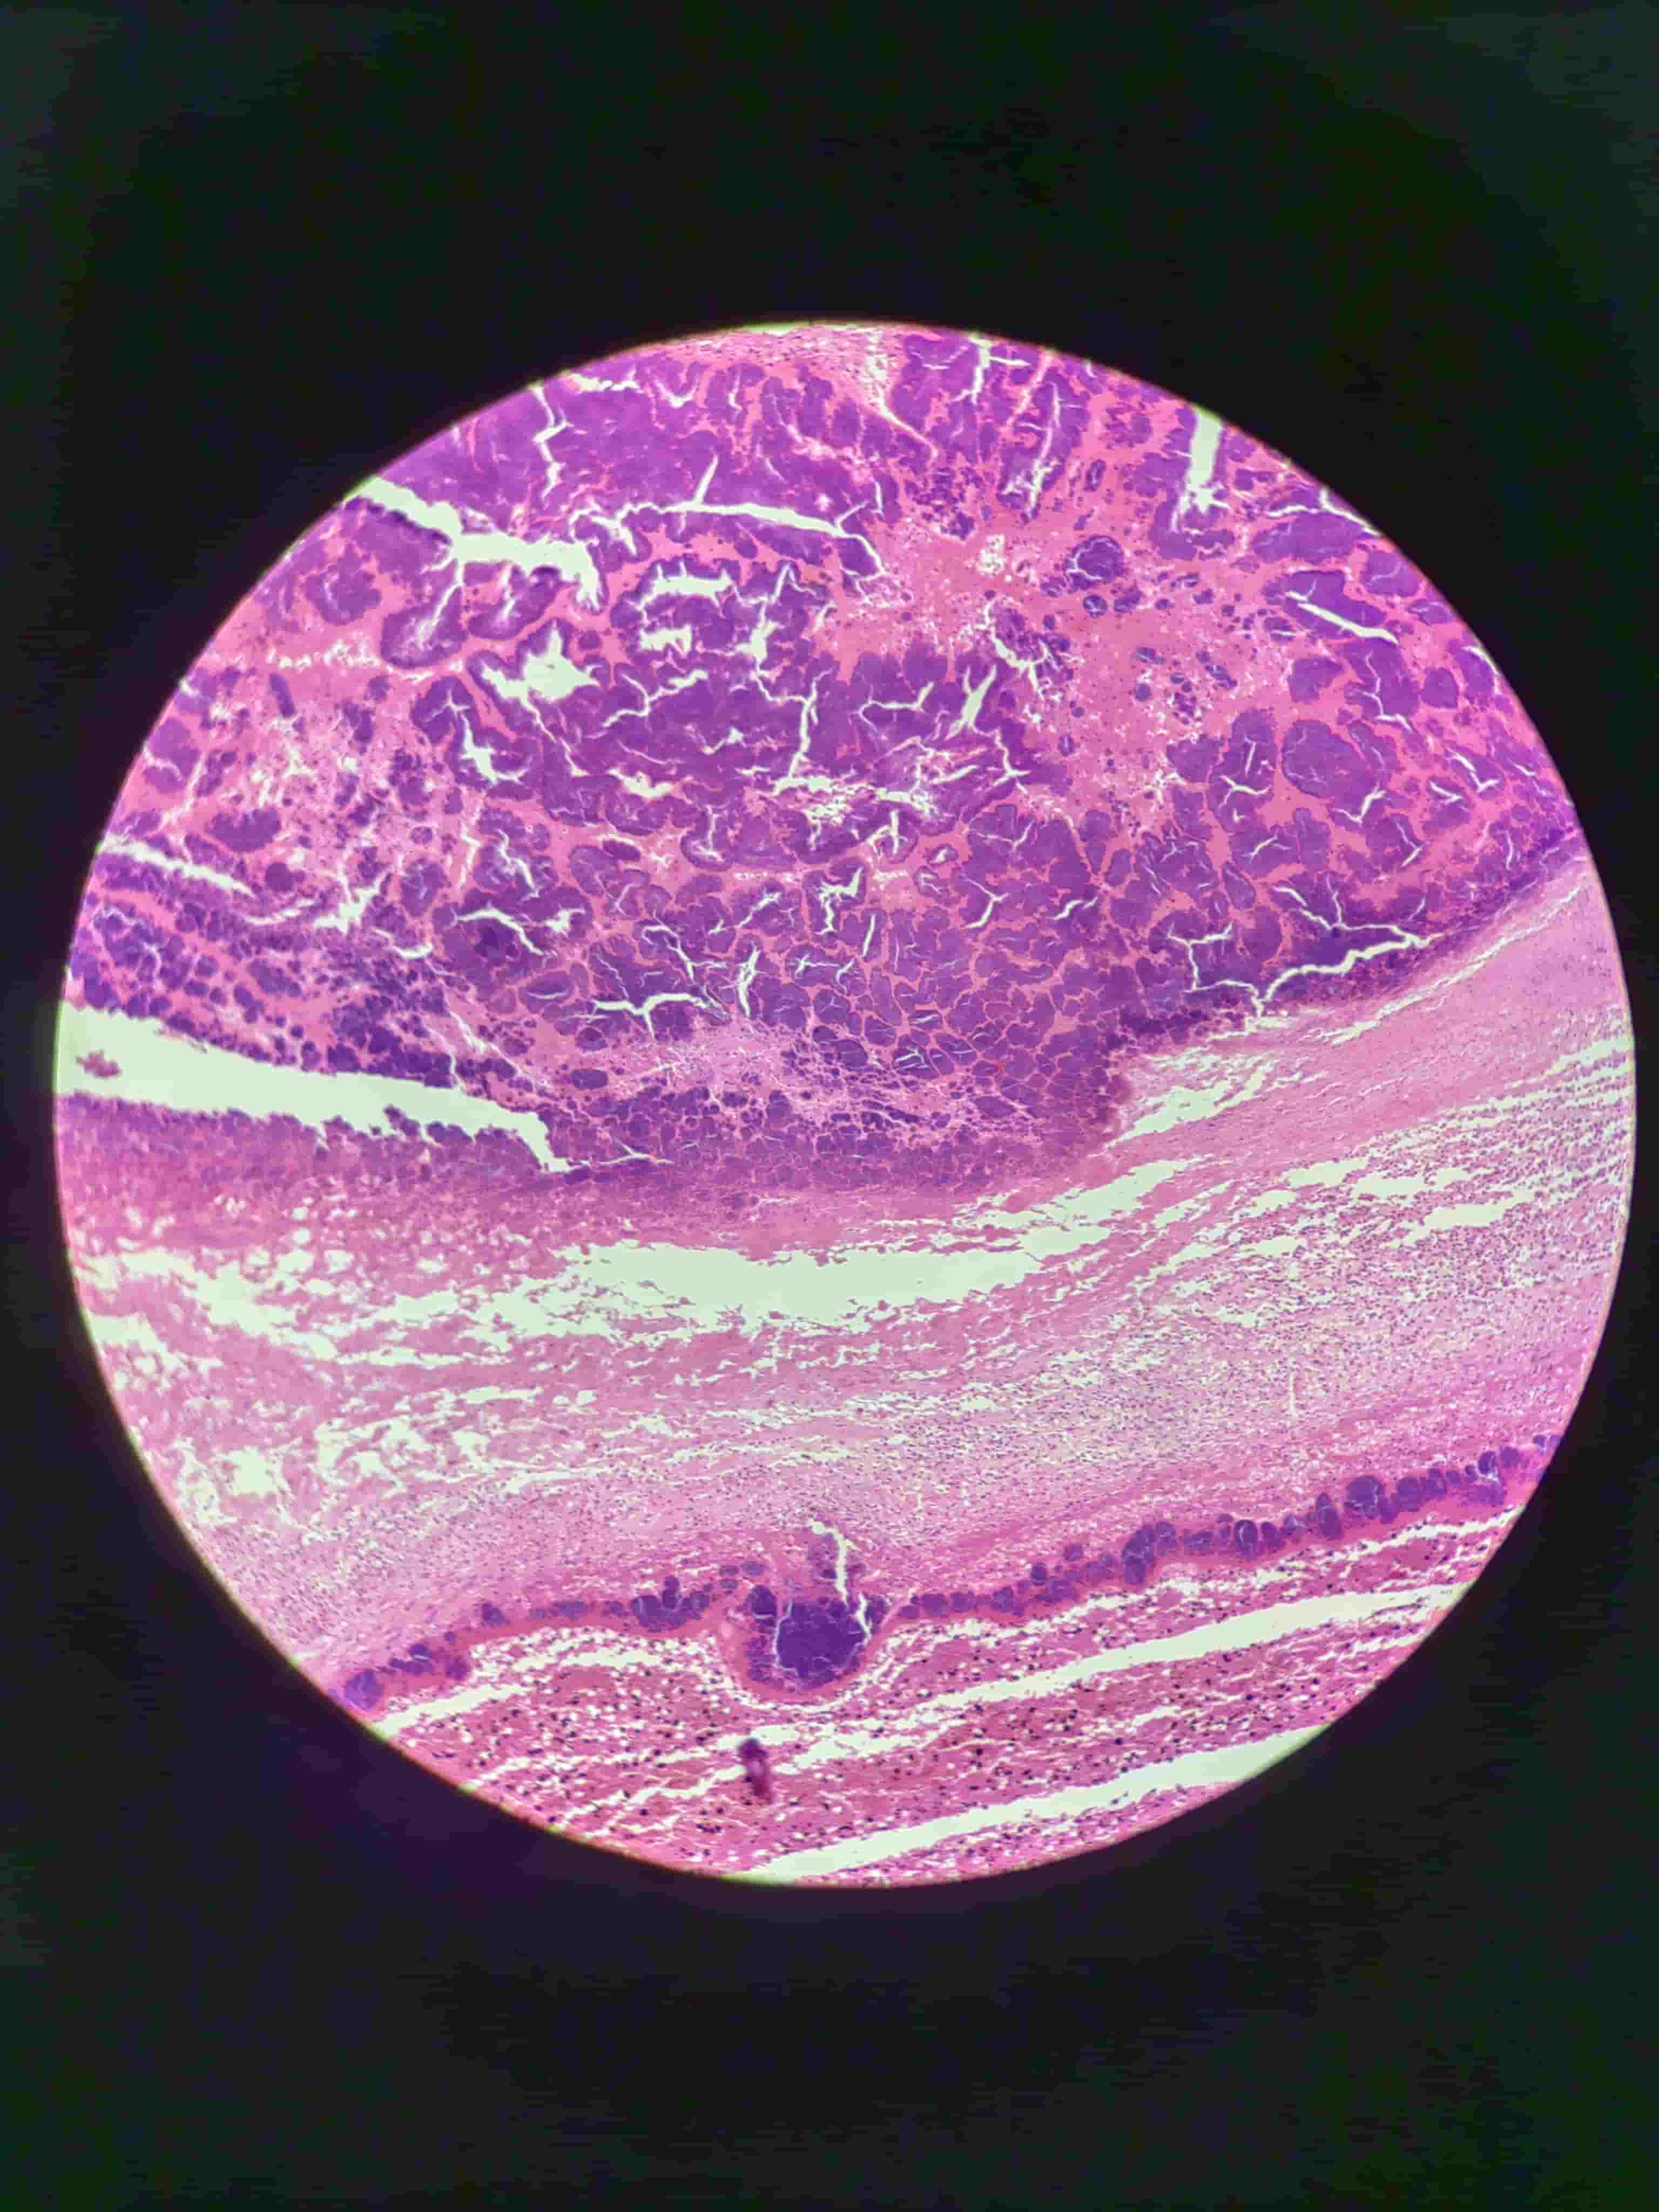

肺干酪样坏死

- 结核病

- 无结构颗粒红染物

- 无组织结构残影,不见核碎屑